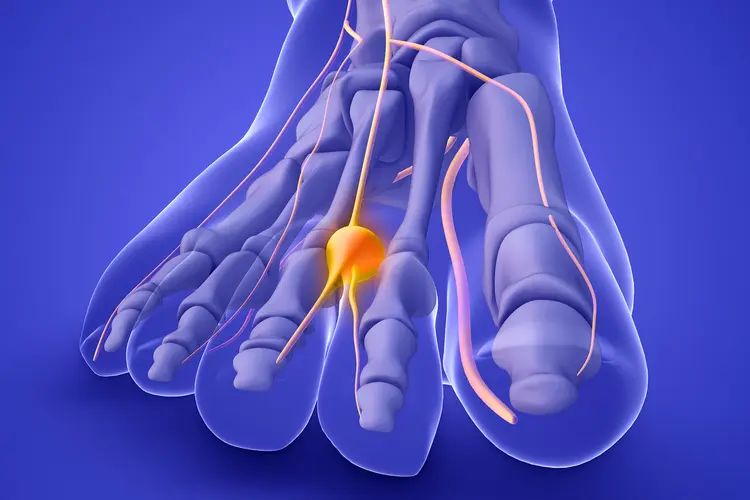

¿Sientes una molestia extraña entre los dedos del pie que no logras identificar? El dolor...